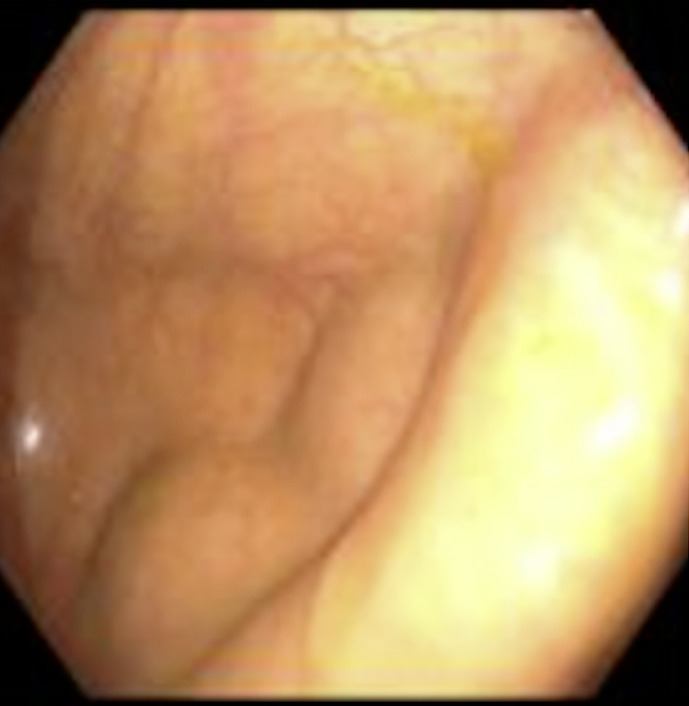

Case presentation: Our patient, a 77-year-old male, underwent an uncomplicated screening colonoscopy and was discharged home after briefly being monitored without any complaints. Later that day, the patient presented to the emergency department complaining of acute generalized abdominal pain. On presentation, the patient was found to be hypertensive and febrile with a distended abdomen with right lower quadrant tenderness on examination. Laboratory investigations noted an elevated white blood cell count with no evidence of acute appendicitis or focal inflammatory changes on contrast-enhanced abdominal and pelvic computer tomography. The patient was subsequently admitted and developed worsening right lower quadrant abdominal pain and distention overnight. Due to this worsening clinical condition, the decision was made to proceed with a diagnostic laparoscopy. After frank pus was found laparoscopically around the cecum and appendix, it was then converted to an exploratory laparotomy. Subsequently, a perforated gangrenous appendix was found with an erythematous and indurated cecum.

Abstract Image